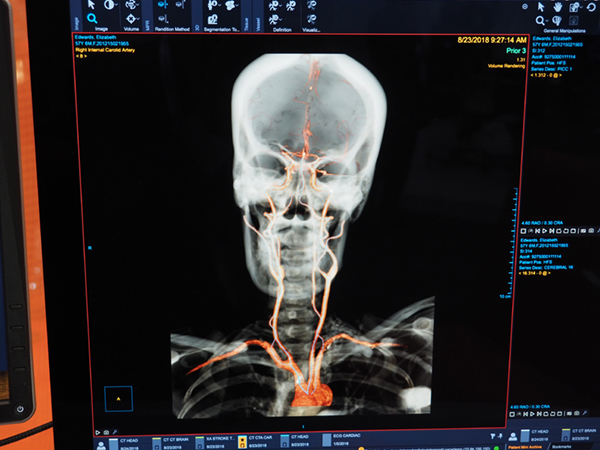

2) Head & Neck Vessel Analysis Protocol

頭頸部の血管を自動的に認識して抽出を行うプロトコール。対象となる画像データについて,バックグラウンドのAIサーバで処理を行うため,従来,血管の抽出に90秒程度かかっていた処理が瞬時に終了する。

Head & Neck Vessel Analysis Protocol(W.I.P.)。頭頸部画像からバックグラウンドでAIが血管を認識して瞬時に表示する。